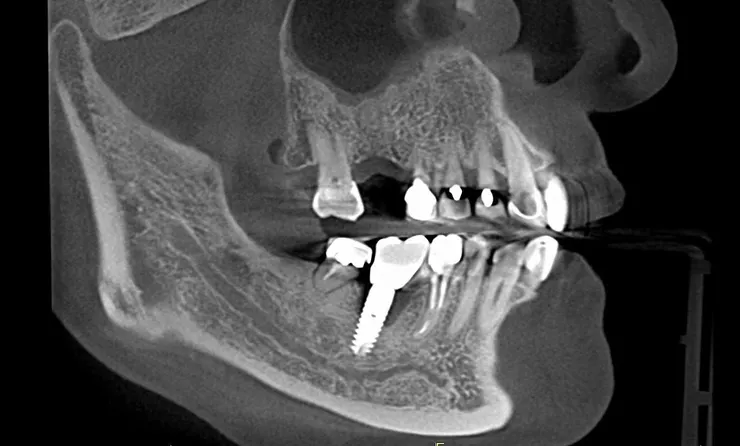

但人工植牙少了這一層天然保護,當患者咬合時產生的應力就會直接傳導到植體與齒槽骨之間,長期下來可能會造成植體周圍的骨組織吸收,進而出現 骨質流失(bone loss) 的情形。

尤其對於本身已有骨質疏鬆體質、或喜歡吃堅果、魷魚絲等較硬食物的患者,傳統的全瓷冠或全鋯冠等高硬度、零彈性的植牙假牙,其實隱藏著不小的風險。

這些材質雖然美觀耐磨,卻不具備任何避震能力,長期使用可能導致植體過早失敗。